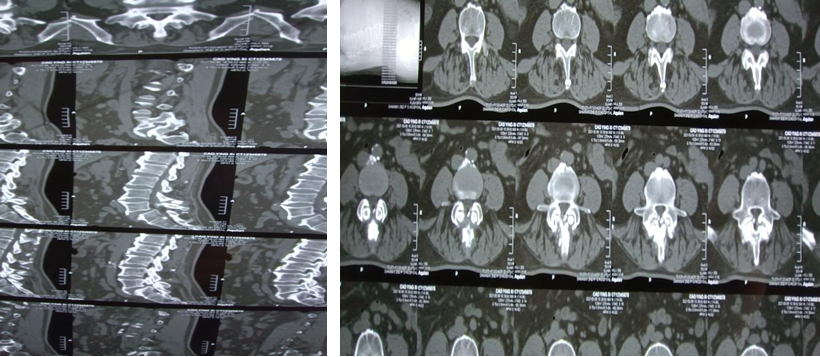

患者术前影像资料